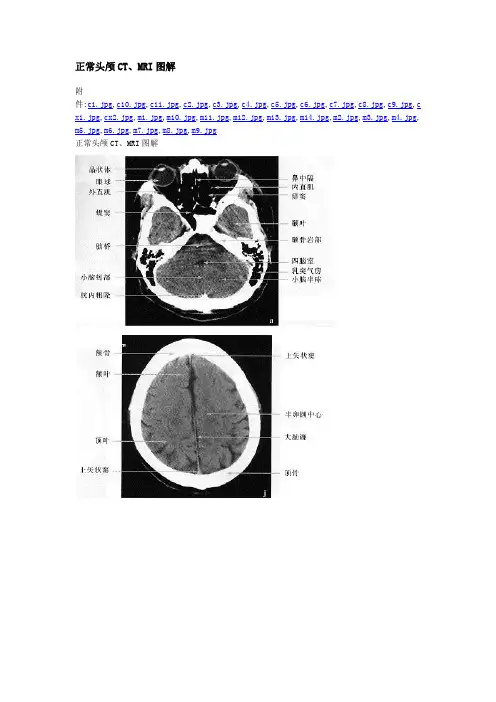

正常头颅CT、MRI图解

头颅CT通常为水平位扫描,常规10层,层厚10mm,信号强度与密度有关:骨>灰质>白质>水>气体,正常情况下血管、垂体、松果体、硬脑膜可强化。